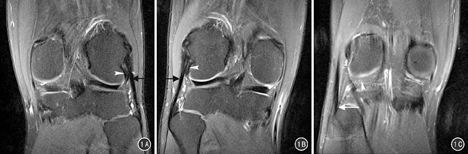

腓侧副韧带位于PLC最浅层,为关节囊外结构,MR冠状位及轴位PDWI序列可清晰显示其形态及走行。腓侧副韧带起于股骨外侧髁后方、腓肠肌外侧头股骨附着处前方,远端斜向后外下附着于腓骨头外侧面和腓骨茎突的前下方;冠状面表现为从股骨远端后外侧到腓骨近端的条带状低信号结构,股骨及腓骨两端附着处较实质部分稍增粗;横断面面表现为类似卵圆形的低信号结构,在附着于腓骨前均加入股二头肌肌腱形成联合腱共同附着于腓骨头。见图1。